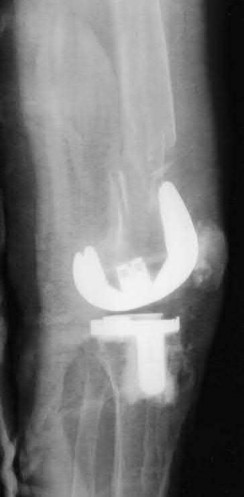

A 65-year-old man presents with anterior knee pain and a feeling of instability during stair climbing 1 year after a primary total knee arthroplasty.

Examination reveals a lateral patellar tilt. CT scan is performed to evaluate component rotation. Which of the following errors in component positioning is most likely responsible for his symptoms?

Explanation

Internal rotation of the femoral component or the tibial component increases the Q angle, leading to lateral patellar maltracking, lateral patellar tilt, and anterior knee pain. External rotation of the components generally improves patellar tracking.